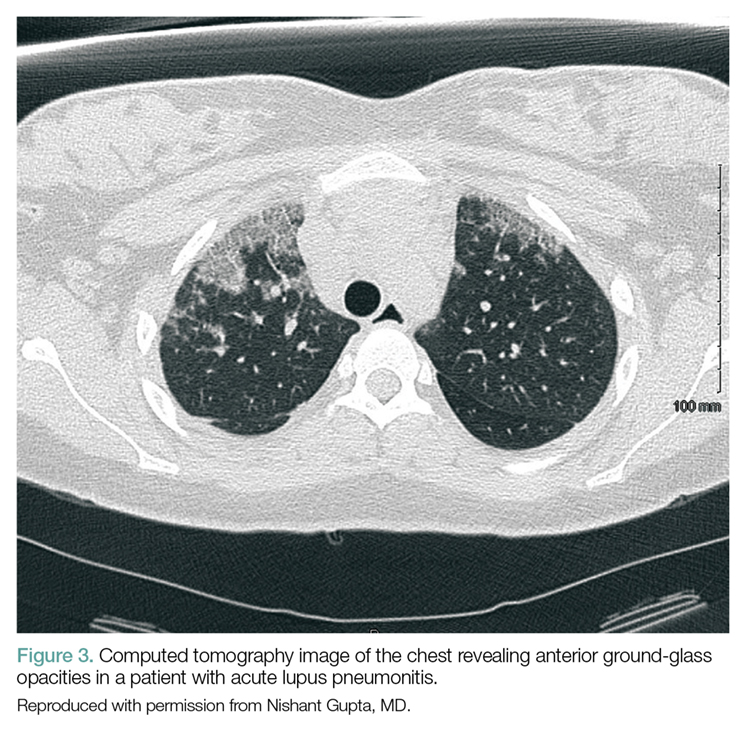

Acute Lupus Pneumonitis. This serious condition may present with severe pneumonia-like signs and symptoms, including fever, cough, dyspnea, hypoxia, and infiltrates on chest radiograph (Figure 3).

Acute lupus pneumonitis is caused by disease flare, and not by infection, although it may not be possible to distinguish it from pneumonia in the ED setting. The mortality rate of acute lupus pneumonitis is as high as 50%, and survivors often progress to chronic interstitial pneumonitis.1